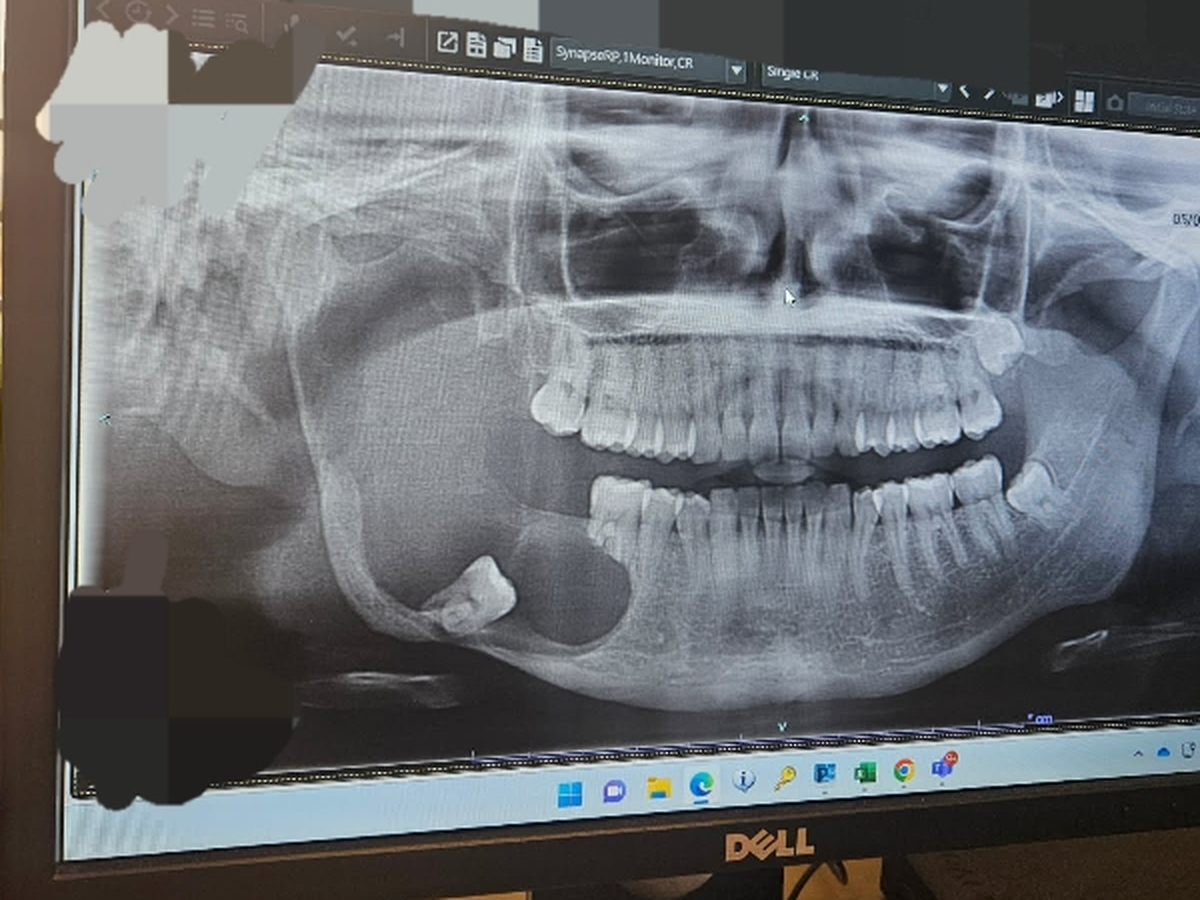

I am raising money for surgery expenses. I met with the surgeon yesterday to go over the latest scans on the tumor in my jaw. Now we're on a deadline to remove it before it reaches my skull base.

My jaw has eroded from the tumor/infection and they will need to remove bone from my leg to rebuild my jaw.